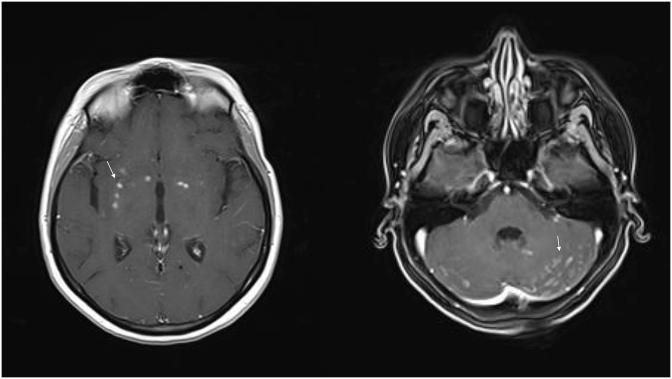

We report a case of a 31-year-old otherwise healthy female with pulmonary cryptococcoma along with cryptococcal meningitis due to molecular type VGI, in Greece. Combined antifungal treatment and surgical excision of pulmonary cryptococcoma yielded a good response.

我们报告了一例31岁的健康女性病例,该患者在希腊患有一种由VGI分子型引起的肺隐球菌瘤合并隐球菌性脑膜炎。联合抗真菌治疗和肺隐球菌瘤手术切除取得了良好疗效。